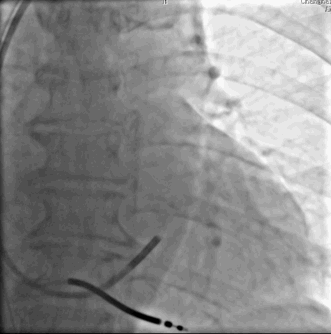

鞘中鞘技术的应用

在美敦力的Attain Select TM+SureValveTM6248VI-130(鞘中鞘)引导下,Sion导丝顺利通过靶静脉第一个夹角,但是在继续推进导丝的时候却发现导丝打圈难以前进。

“猪尾圈”状靶血管导丝无法前进,容易弹出

下一步如何办?

球囊辅助技术的应用

美敦力2.0*15mm球囊前端扩张4ATM引导鞘中鞘进入靶血管中段---优势:

•防止血管夹层,穿孔

•提供支撑力

球囊辅助技术

•打圈的导丝